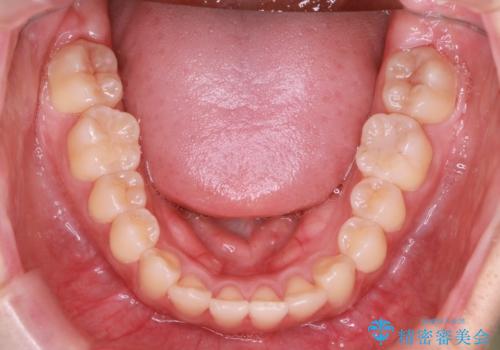

- 前歯のガタガタを主訴に来院されました。

インビザラインも提案しましたが、装着時間を確実に確保できるか不安ということもありワイヤー矯正を希望されました。